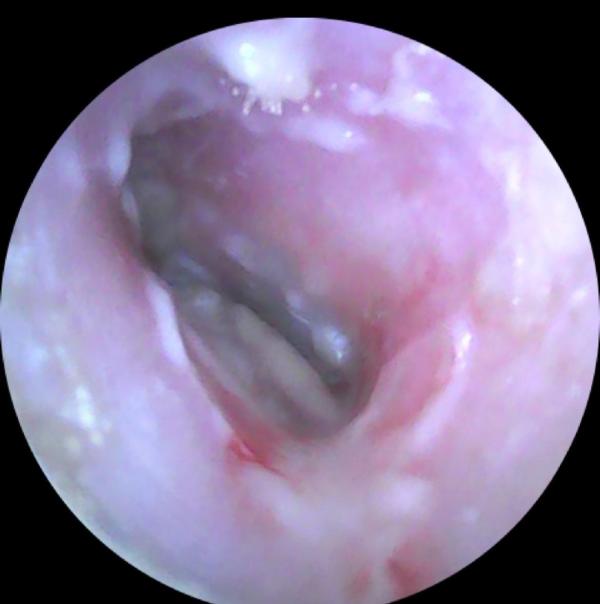

Отомикоз -грибковое поражение уха.

На фото эндоскопическое изображение наружного слухового прохода. Кожа наружного слухового прохода гиперемирована,отечна.На некоторых участках можно увидеть мицелии грибов.